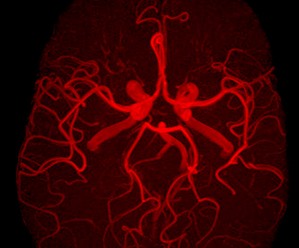

Сосудистые психозы

Психопатологические проявления в виде острых психозов могут возникать на любом этапе сосудистого процесса, даже в состоянии деменции. Ф. Штерн (1930) описал «артериосклеротические состояния спутанности». Такие психозы характеризуются рядом общих клинических свойств. Прежде всего, возникающие в структуре этих психозов синдромы помрачения сознания как реакции экзогенного типа отличаются атипичностью, невыраженностью всех своих компонентов, синдромальной незавершенностью. Проявления острых сосудистых психозов далеко не всегда соответствуют наиболее типичным картинам делирия, аменции, сумеречного состояния, онейроида и другим, что позволяет вполне обоснованно квалифицировать их как состояния «спутанности» (М. Блейлер, 1966). Другим свойством сосудистых психозов можно считать то, что острые психотические эпизоды бывают довольно часто кратковременными, возникают эпизодически, продолжаются не больше нескольких часов. Как правило, такой эпизод разворачивается в ночное время, а днем больные могут находиться в ясном сознании, без психотических расстройств. Общим свойством сосудистых психозов является также их повторяемость, подчас неоднократная. Прежде всего это относится к ночным состояниям спутанности. Течение острых сосудистых психозов отличается от течения симптоматических психозов другой этиологии — таких, как алкогольный делирий, острый травматический психоз. Так, в динамике белой горячки нарастание тяжести заболевания выражается чаще всего углублением самого делириозного синдрома (переход «профессионального делирия» в мусситирующий), а при острых сосудистых психозах различные синдромы измененного сознания могут сменять друг друга (после делириозного синдрома может следовать аментивный и т.д.).